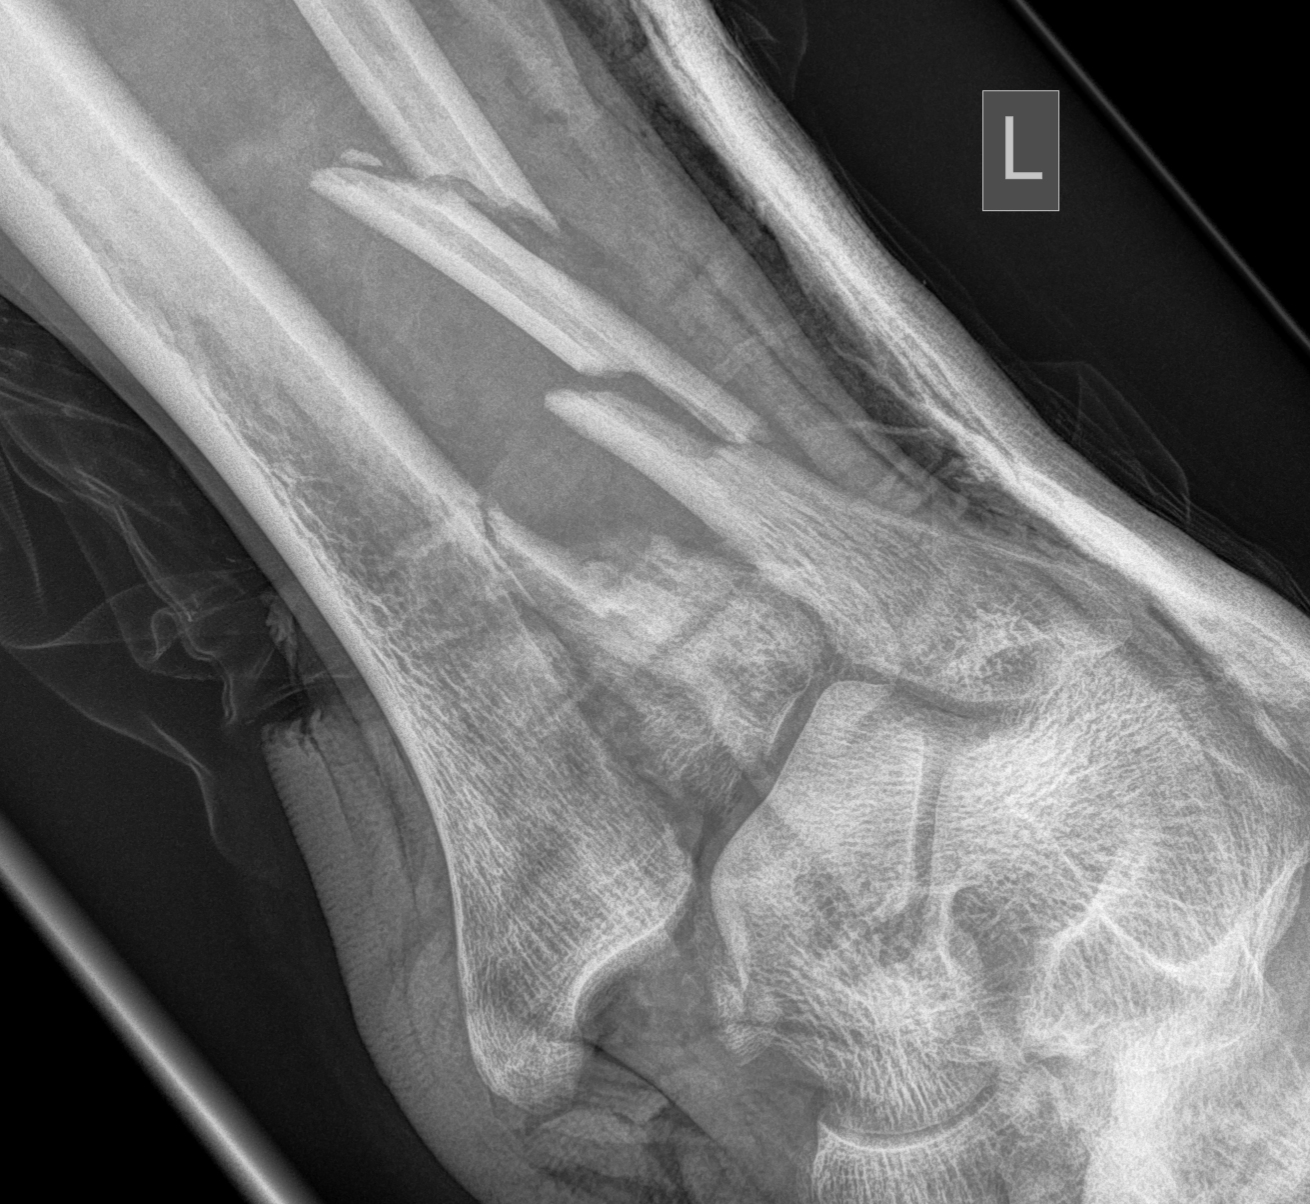

Severe Tibial PlafondAnterolateral fragment and valgus injuryTibial Plafond External Fixator

Tibial Plafond Pre External Fixator APTibial Plafond Pre External Fixator LateralTibial Plafond Post External Fixator APTibial Plafond Post External Fixator Lateral

Anterolateral / anterocentral approach

Indication

- anterolateral / Chaput fragment

- valgus configuration